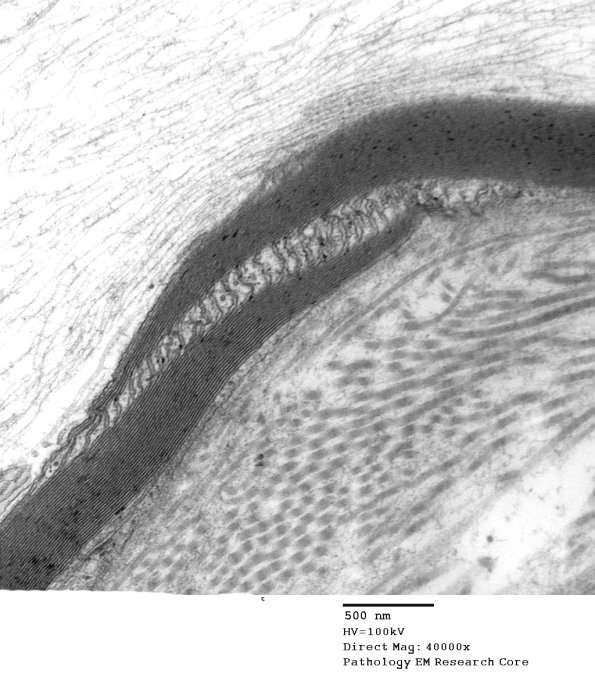

3B2,3 Higher magnification images of the SLC showing a common single microtubule content (arrow, 3B3).